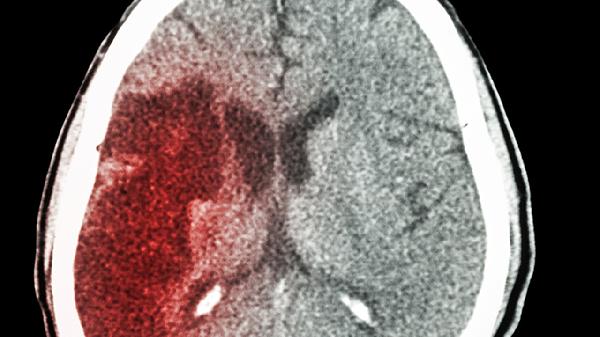

小脑出血后恢复期要特别注意这些事项

小脑出血进入恢复阶段后,需要注意血压管理、并发症预防、康复锻炼、饮食调整以及定期检查。在恢复期做好护理工作,对患者的康复效果有重要影响,需要从多个方面入手进行综合干预。

恢复阶段要定期做头部CT或MRI检查,了解出血是否已经吸收。通常第一次复查是在出院后一个月左右,之后根据病情每三到六个月复查一次。同时也要关注肝肾功能和电解质水平,看看是否有药物不良反应。如果出现头晕加重、走路不稳等新症状,要及时去医院检查。长期随访可以帮助早期发现和处理潜在问题。